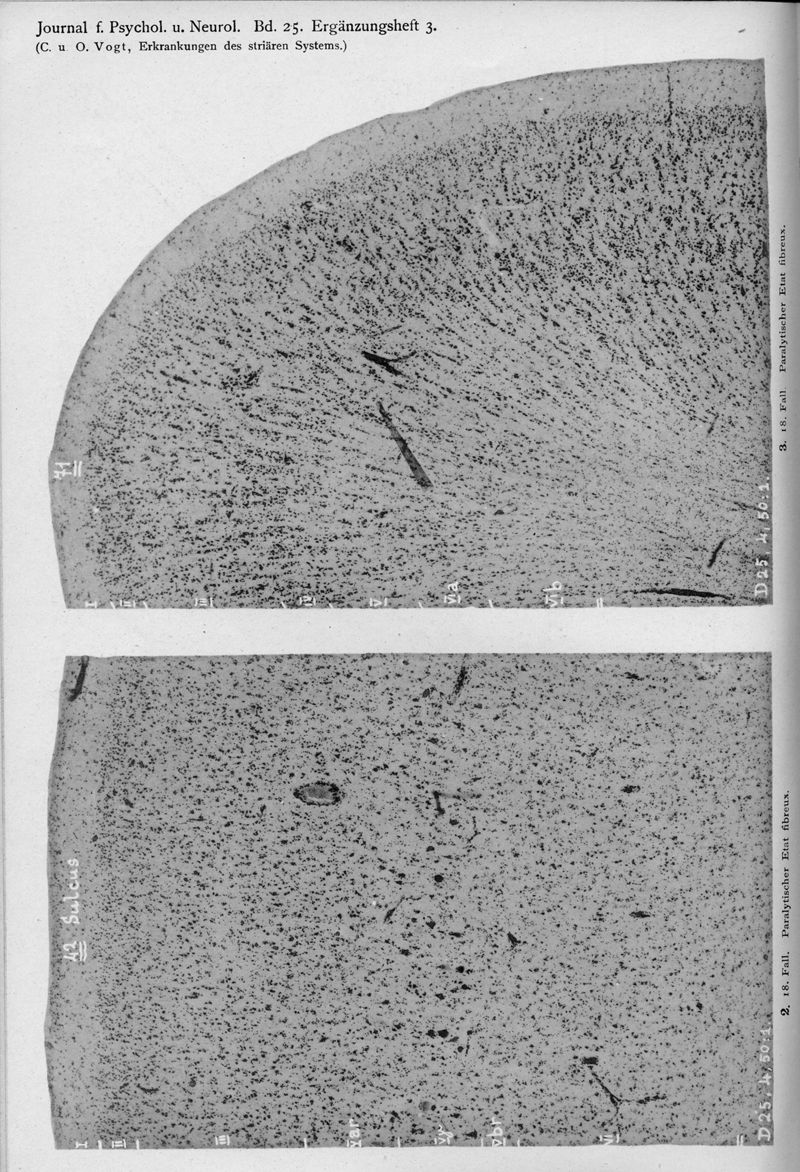

VOGT, Cécile / VOGT, O.

In : Journal für Psychologie und Neurologie,

1920, Vol. 25, pp. 627-846